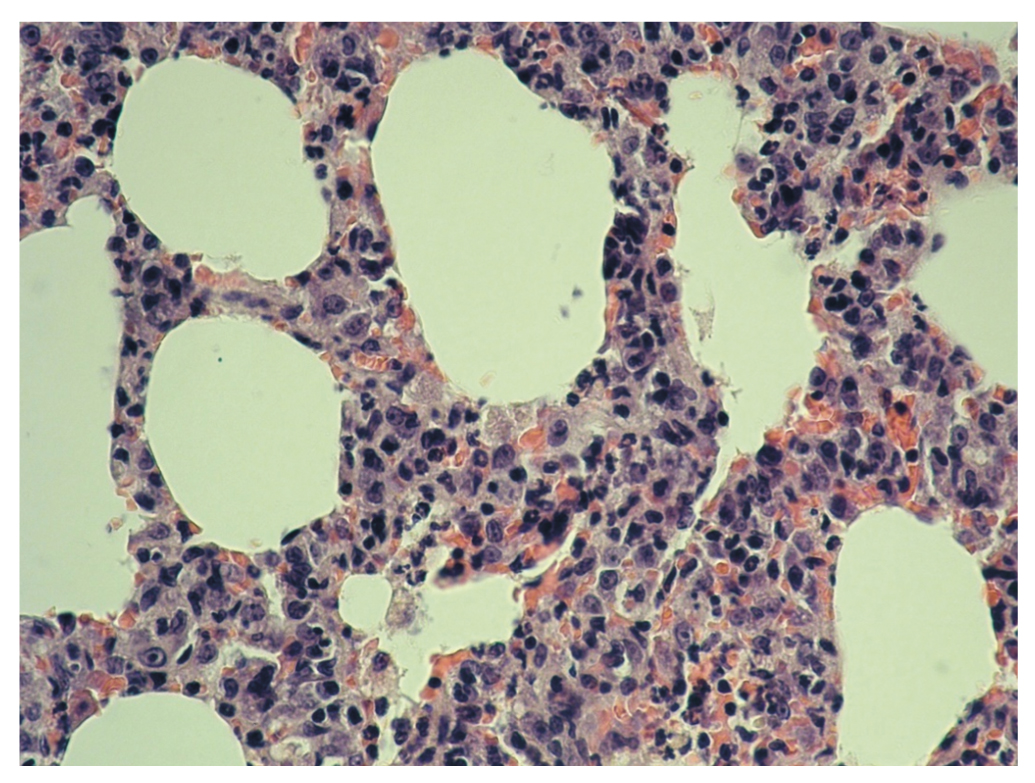

Рис. 2. Легкое крысы группы 2 (баклофен, 85 мг/кг). Инфильтрация межальвеолярных перегородок лейкоцитами. Увеличение 400. Окрашивание гематоксилином и эозином

В легких животных, получавших комбинацию баклофена (в дозе 85 мг/кг) и этанола (7 мл/кг 40% этанола), просветы альвеол свободны, не расширены. Субплеврально расположены небольшие участки эмфиземы. Отмечали большое количество «пластинчатых» дистелектазов (рис. 3).

Рис. 3. Легкое крысы группы 3 (баклофен, 85 мг/кг + этанол). Утолщение межальвеолярных перегородок за счет отека, инфильтрация межальвеолярных перегородок лейкоцитами. Увеличение 400. Окрашивание гематоксилином и эозином

В участках дистелектазов капилляры в межальвеолярных перегородках были полнокровны. В просветах части альвеол наблюдали скопление макрофагов. В легочных артериях наблюдали сладжи. Некоторые бронхиолы имели звездчатую форму. На территории межальвеолярных перегородок отмечали лейкоцитарную инфильтрацию. В просвете некоторых бронхиол — секрет, чего не было отмечено в группе, получавшей баклофен в виде монопрепарата (рис. 4).

Наблюдали утолщение межальвеолярных перегородок (рис. 5).

Рис. 5. Легкое крысы группы 3 (баклофен, 85 мг/кг + этанол). Утолщение межальвеолярных перегородок за счет отека, инфильтрация межальвеолярных перегородок лейкоцитами. Увеличение 400. Окрашивание гематоксилином и эозином

Достоверным в этой группе можно считать наличие полнокровия венул и капилляров, сладжа, эмфиземы, ателектазов и дистелектазов, клеточную реакцию (инфильтрацию лейкоцитами), утолщение межальвеолярных перегородок за счет отека, а также наличие секрета в просвете бронхиол.